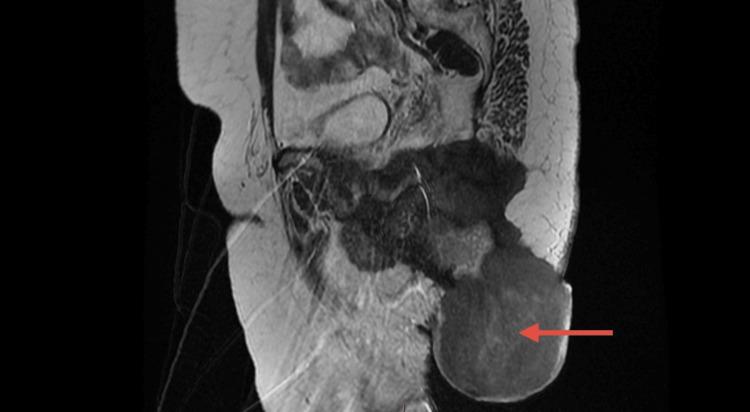

This report presents the case of a 52-year-old woman with a recurrent perianal mass, initially diagnosed as a benign GCT. Despite surgical resection, the tumor later metastasized to the lungs and lymph nodes, indicating malignant transformation. Imaging and histological analysis confirmed the malignancy, with cellular atypia and metastasis. The patient declined further treatment and passed away shortly thereafter. This case underscores the potential for malignant transformation in GCTs, particularly in recurrent cases. While surgical removal with clear margins remains the standard approach, malignant GCTs often present a poor prognosis due to high rates of recurrence and metastasis, with limited response to chemotherapy and radiation therapy.

本报告介绍了一名52岁女性复发性肛周肿块的病例,最初诊断为良性生殖细胞肿瘤(GCT)。尽管进行了手术切除,但肿瘤后来转移至肺部和淋巴结,提示发生了恶性转化。影像学和组织学分析证实了恶性肿瘤的存在,伴有细胞异型性和转移。患者拒绝进一步治疗,此后不久去世。该病例强调了GCTs发生恶性转化的可能性,尤其是在复发病例中。虽然切缘清晰的手术切除仍是标准治疗方法,但恶性GCTs由于复发和转移率高,对化疗和放疗反应有限,往往预后较差。